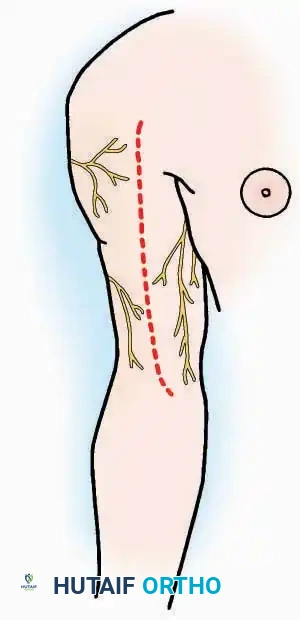

A pneumatic tourniquet should be universally employed in extremity surgery unless specifically contraindicated (e.g., severe peripheral vascular disease, sickle cell trait, or compromised soft-tissue envelopes). The exsanguinated, dry field facilitates precise dissection, minimizes traumatic tissue handling, and significantly reduces operative time. Furthermore, a bloodless field is critical for the reliable identification and preservation of delicate cutaneous nerves, which often serve as anatomical landmarks for deeper internervous planes.

Even with temporary ischemia, an electrocautery unit must be utilized to meticulously coagulate small vessels crossing the incision, preventing postoperative hematoma formation upon tourniquet deflation. In axial or proximal regions where a tourniquet is unfeasible (e.g., shoulder, hip, pelvis), electrocautery becomes the primary modality for maintaining visualization and minimizing blood loss.